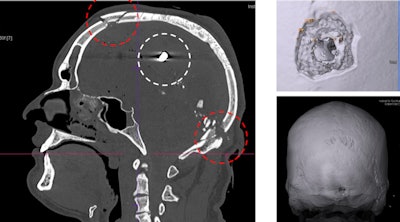

Gunshot injuries can be perfectly visualizised in 3D for court cases. Here, images show a gunshot with entrance wound in the neck area and bullet ricochet effect in the inner frontal part of the skull."Behind every body there is a family for whom we strive to answer questions without cutting up their loved ones," Thali said.